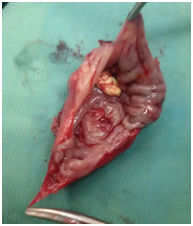

All six patients were symptomatic Four of patients were male. Age of patients was 65 to 80years. Four of patients came with dysphasia aspiration, halitosis, and malnutrition and regurgitation, one of this patient present three period with aspiration pneumonia and hospital admission. One of patients underwent endoscopic diverticulotomy and 24 hour after this procedure present with odynophagia, fever and neck subcutaneous emphysema With B-swallow perforation of diverticula was demonstrated, this patient underwent neck exploration and diverticulectomy and drainage. Diagnostic tools of five cases was B-swallow and esophagoscopy (Figures 1-5). One came with food marital retention and pain and neck mass tender mass. One patients referred with erithem, redness and criptation of neck with diagnosis of diverticulitis (Figures 6 & 7). Two cases underwent flexible endoscopic diverticulotomy, one failed and another ones complicated with perforation. The most common surgical approaches was diverticulectomy and myotomy in four patients (Figures 8 & 9). Food debris was present in one patient (Figure 10). Two of patients underwent diverticulectomy without myotomy. Complication and mortalities were zero. In two years flow-up, Outcome was good.

Figure 10 Show swallow debris in the pouch of huge Zenker's diverticulum.